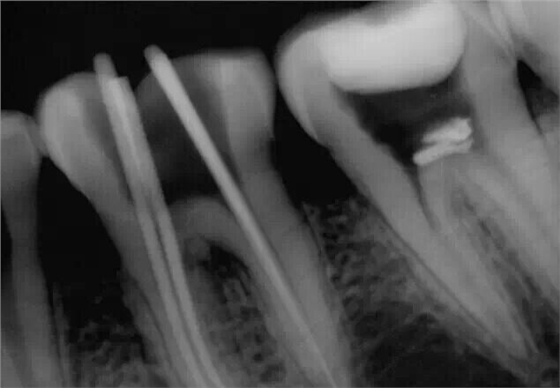

忘記照術前片了,補一張去腐后的照片。在進行根管預備的時候D7遠中出現(xiàn)器械分離

沒辦法只能掏針了,先形成側方通路,然后用超聲慢慢往出震。

震出一半時照的X片